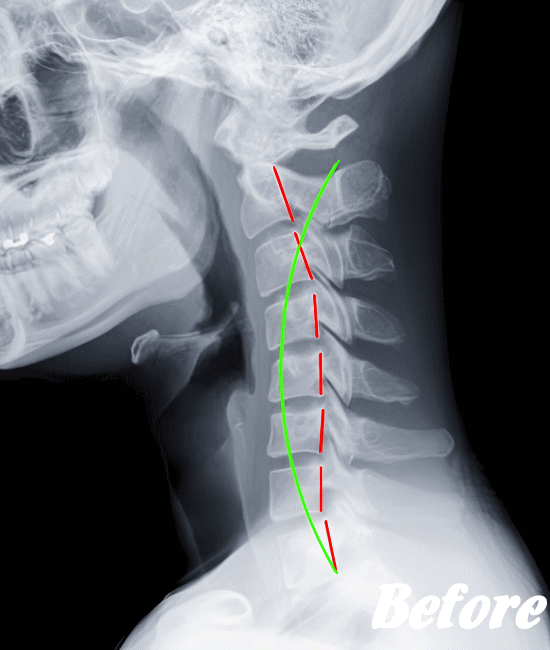

したがって、まずは病院にて検査をお勧めします。検査で問題なければ、骨のズレを調節するための施術を受けてみてはいかがでしょうか。

HALOカイロプラクティック☆平和島整体院では、骨盤(仙腸関節)から背骨(腰椎、胸椎、頸椎)、肋骨(肋椎関節)、肩甲骨(肩甲胸郭関節)などを調整し緩めることで、首(頚椎)にかかる負担を取り除き、可動域を良くして痛みを解消していきます。

首や肩周りの症状では、肩甲胸郭関節(肩甲骨周辺)を調整することは必須です。

寝違えやムチ打ちは、速効矯正・即効施術の【体の整体】の適応になります。